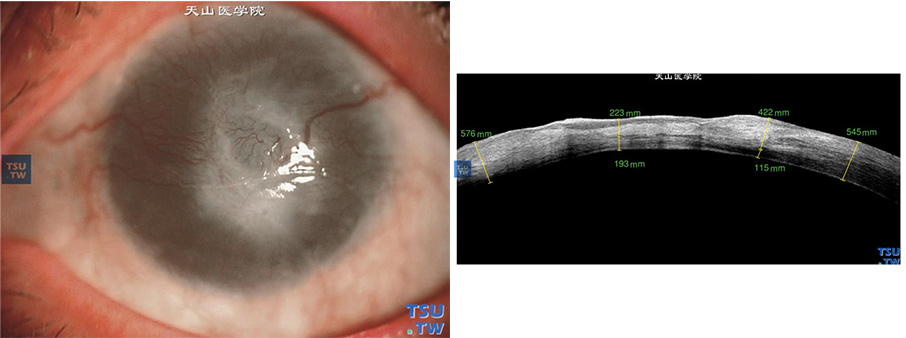

患者因结角膜干燥,行角膜缘干细胞移植术后5年,病情复发,角膜表面新生血管膜,中央角膜溃疡,角膜基质水肿、浑浊;角膜基质薄厚不均,角膜基质影像密度明显升高,但内皮层影像尚光滑连续